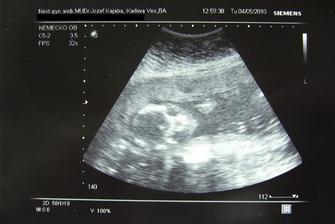

♥ 04.05.2010 sme boli na bežnej poradni a všetko je ok. Dokonca naše milované chlapčiatko videl aj MM. Na ďalšiu poradňu ideme o tri týždne a dovtedy musíme stihnúť kopec vyšetrení